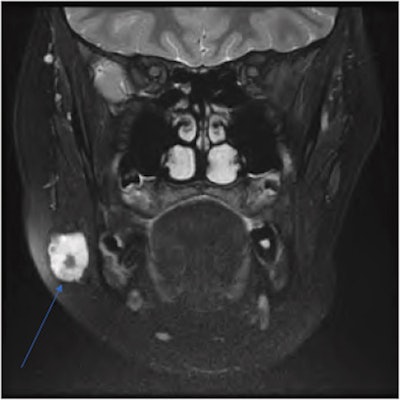

An arrow labels a well-circumscribed, T2 hyperintense lesion on a coronal T2 MRI neck scan. The lesion has a focal area of low intensity internally, located in the right parotid gland.Due to the lesion's unknown origin and concerns that it may be a possible neoplasm, a multidisciplinary team recommended an excision biopsy. The girl underwent a superficial parotidectomy to include the mass, which had multiple phleboliths clumped inside.